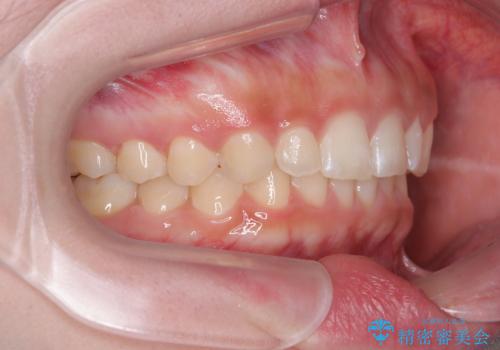

- 前歯のデコボコとディープバイトを気にして来院された患者様です。

左上前歯前方に飛び出しているため、歯列全体が前方に移動している状態でした。

短期間で確実に仕上げたいとのことで、アンカースクリューと補助装置を併用して歯列の後方移動を図り、ワイヤー装置にて矯正治療を行うこととしました。

左上の歯列は補助装置により速やかに移動し、1年程度で奥歯の咬み合わせが改善され、1年3ヶ月の短期間でしっかりと仕上げることができました。